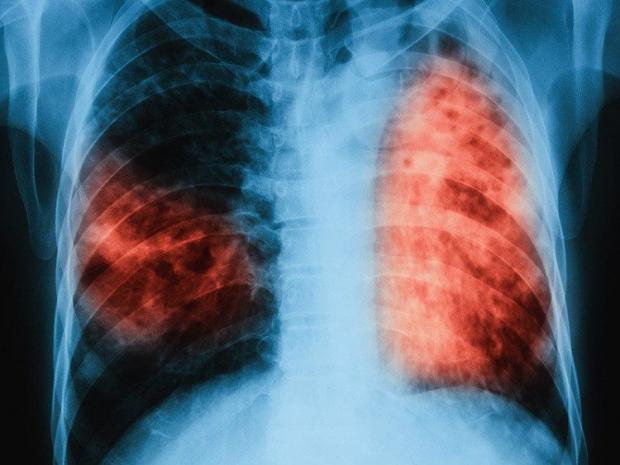

Bệnh lao phổi - một trong tứ chứng nan y ngày nay đã không còn là bệnh khó chữa. Nhưng không vì thế mà nó bớt nguy hiểm và khả năng chúng ta mắc phải bệnh lao thực sự cao đến giật mình.

Tuy nhiên, nói cách nào đi nữa thì lao phổi cũng là một trong những căn bệnh nguy hiểm nhất trên thế giới. Ước tính chỉ trong năm 2015, đã có 1,8 triệu người chết vì căn bệnh này.

Khác với các loại khuẩn khác, người ta có thể nhiễm khuẩn lao tuberculois (TB) mà không phát bệnh. Nhưng trái với quan niệm hiện nay là chỉ 10% người nhiễm sẽ phát bệnh thì thực ra tất cả chúng ta đều có nguy cơ, vì thậm chí hàng chục năm sau khuẩn lao vẫn có thể trực chờ tấn công cơ thể nếu gặp điều kiện thích hợp.

Kết quả, số lượng người đang nhiễm khuẩn lao rơi vào khoảng 1,7 tỉ người - tức là gần 1/4 dân số thế giới hiện nay. Về tỉ lệ thì có thể giảm sút, nhưng con số thực tế vẫn đang ở mức cao.

80% số này đến từ các quốc gia tại châu Á và châu Phi, và thường tập trung ở nhóm người cao tuổi. Đáng chú ý, gần 100 triệu trẻ em hiện nay cũng đang nhiễm TB - con số vượt cả tổng số người tại Đức.

Bên cạnh đó, Pete Dodd - người đứng đầu nghiên cứu cho rằng việc loại bỏ bệnh lao cần được ưu tiên, vì đây vẫn là một căn bệnh cực kỳ nguy hiểm. Nó vẫn đang lây nhiễm cho gần 2 tỉ người trên thế giới, gây ra 1,8 triệu trường hợp tử vong mỗi năm.